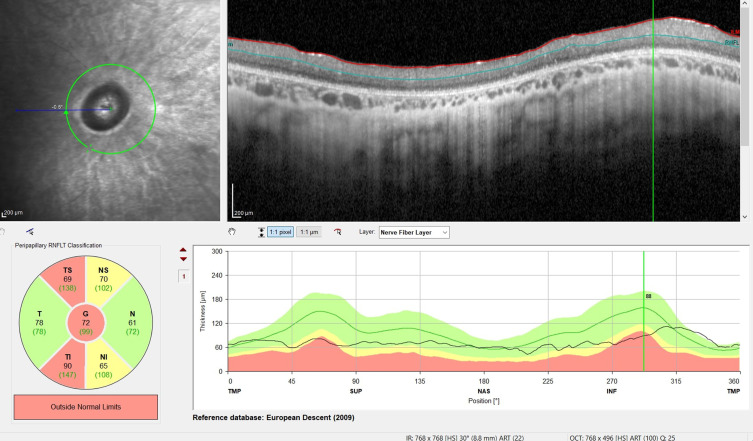

目的:研究晚发型神经元类脂膜脂质沉着症2型(CLN2)患者视网膜周围神经纤维层(pRNFL)是否存在变性,并评估光学相干断层扫描(OCT)评估的pRNFL厚度作为CLN2疾病进展的生物标志物的作用:这项回顾性队列研究共纳入了20名经遗传学和酶学确诊为晚发型CLN2疾病患者的40只眼睛。所有患者均接受了每两周一次、每次 300 毫克的脑室内酶替代治疗(cerliponase alfa)。在全身麻醉的情况下,使用光谱域 OCT(德国海德堡海德堡工程公司)进行 OCT 成像。PRNFL 厚度和视网膜中央厚度 (CRT) 值由海德堡 Eye Explorer 软件手动确认。相应的儿科数据来自 DEM-CHILD 数据库。计算了pRNFL和CRT值、检查时的年龄、威尔-康奈尔晚期婴儿神经元类色素沉着症量表(Weill Cornell LINCL)和汉堡运动与语言量表(HML)之间的斯皮尔曼相关系数(rs):20 位患者中有 14 位接受了连续检查,共获得 84 次 OCT 扫描和 42 次威尔-康奈尔 LINCL 和 HML 量表评分。平均年龄为 6.90 岁,平均随访时间为 1.38 年。全球 pRNFL(G-pRNFL)平均厚度为 77.02 μm,与健康儿童的标准值(106.45 μm;p < 0.0001)相比明显下降。G-pRNFL 与检查时的年龄(rs = - 0.557,p < 0.01)、威尔康奈尔 LINCL 量表(rs = 0.849,p < 0.01)和 HML 量表(rs = 0.833,p < 0.01)呈显著相关。重复测量结果表明,大多数患者的 pRNFL 厚度会随着时间的推移而下降:结论:晚发型CLN2患者无论是否存在视网膜外层变性,其pRNFL都会表现出早发的进行性损失,这凸显了pRNFL作为晚发型CLN2患者视网膜病变的独立眼部生物标记物的潜力。

Patients and methods: Forty eyes of 20 patients with genetically and enzymatically confirmed diagnosis of late-infantile CLN2 disease were included in this retrospective cohort study. All patients received 300 mg of intracerebroventricular enzyme replacement treatment (cerliponase alfa) once every two weeks. OCT imaging was performed under general anesthesia using spectral domain OCT (Heidelberg Engineering, Heidelberg, Germany). PRNFL thickness and central retinal thickness (CRT) values were manually confirmed with the Heidelberg Eye Explorer software. Corresponding pediatric data were extracted from the DEM-CHILD database. Spearman correlation coefficient values (rs) were calculated between pRNFL and CRT values, age at examination, the Weill Cornell Late Infantile Neuronal Ceroid Lipofuscinosis (Weill Cornell LINCL) Scale and the Hamburg Motor and Language (HML) Scale.

Results: Fourteen of 20 patients underwent serial examinations resulting in a total of 84 OCT Scans and 42 Weill Cornell LINCL and HML Scale scores. Mean age was 6.90 years and mean follow-up time was 1.38 years. Mean global pRNFL (G-pRNFL) thickness was 77.02 μm presenting a significant decrease compared to normative values from healthy children (106.45 μm; p < 0.0001). G-pRNFL displayed significant correlations towards age at examination (rs = - 0.557, p < 0.01), the Weill Cornell LINCL Scale (rs = 0.849, p < 0.01), and the HML Scale (rs = 0.833, p < 0.01). Repeated measurements indicated decreases in pRNFL thickness over time in most patients.

Conclusion: Patients with late-infantile CLN2 disease exhibit early onset progressive pRNFL loss regardless of outer retinal degeneration, highlighting the potential of pRNFL as an independent ocular biomarker for retinal pathology in late-infantile CLN2 disease.